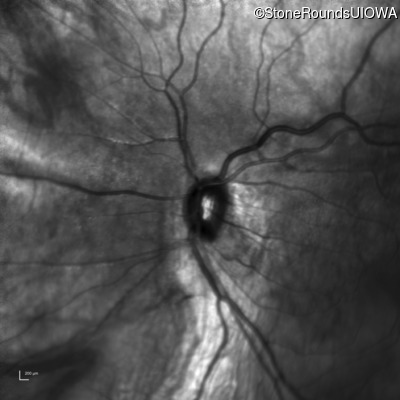

Infrared Fundus Photograph - Right - 20/40 +2

Exemplar